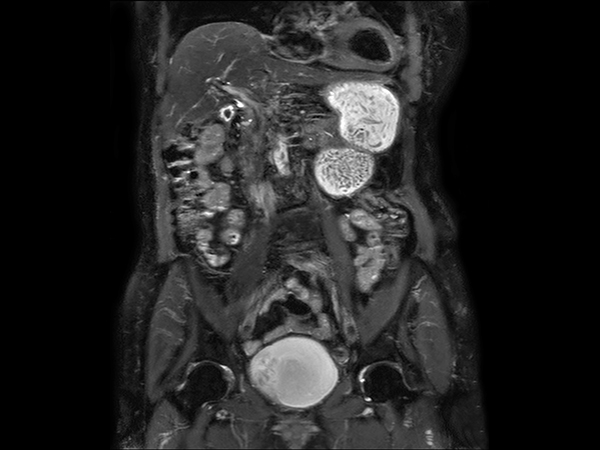

Coronal T2w TSE dS SENSE = 5, FOV 480 mm